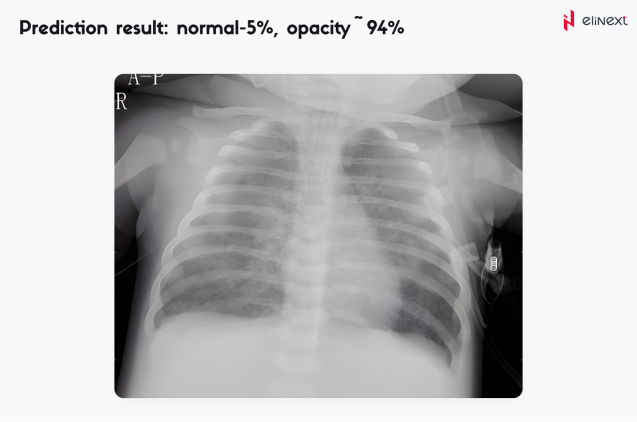

An automated pneumonia diagnosis tool, a part of a comprehensive telehealth platform, was designed to help identify signs of pneumonia using machine learning techniques. For that, the tool leverages the convolutional neural network Inception v3 developed by Google Research Team. The developed model was further trained using a curated data set of lung images.

The resulting algorithm uses binary identification — if it identifies 80% of lungs as unaffected, it will mark the lungs as healthy. For anything less than 80%, the model assumes the lungs might be affected and require expert medical attention. In addition to significantly reducing human errors, the solution can alleviate the burden of healthcare professionals.

An automated pneumonia diagnosis tool